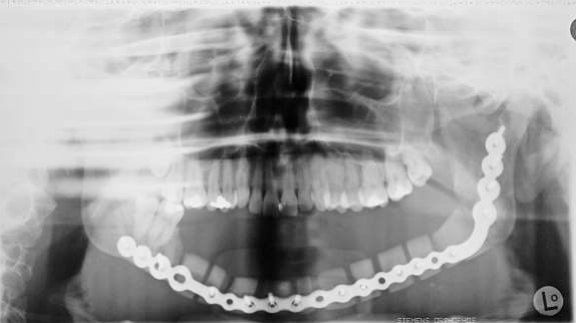

Fig 5:Juni 1997: resection of the lower jaw regio 46-37, plate for reconstruction, AAA-bone histology: ossyfying fibroma turned into osteosarkoma grade III, resection non in sano

Fig 6: März 1998: reconstruction of the lower jaw with vascular stalked fibula from left side

Figure 5

Figure 6